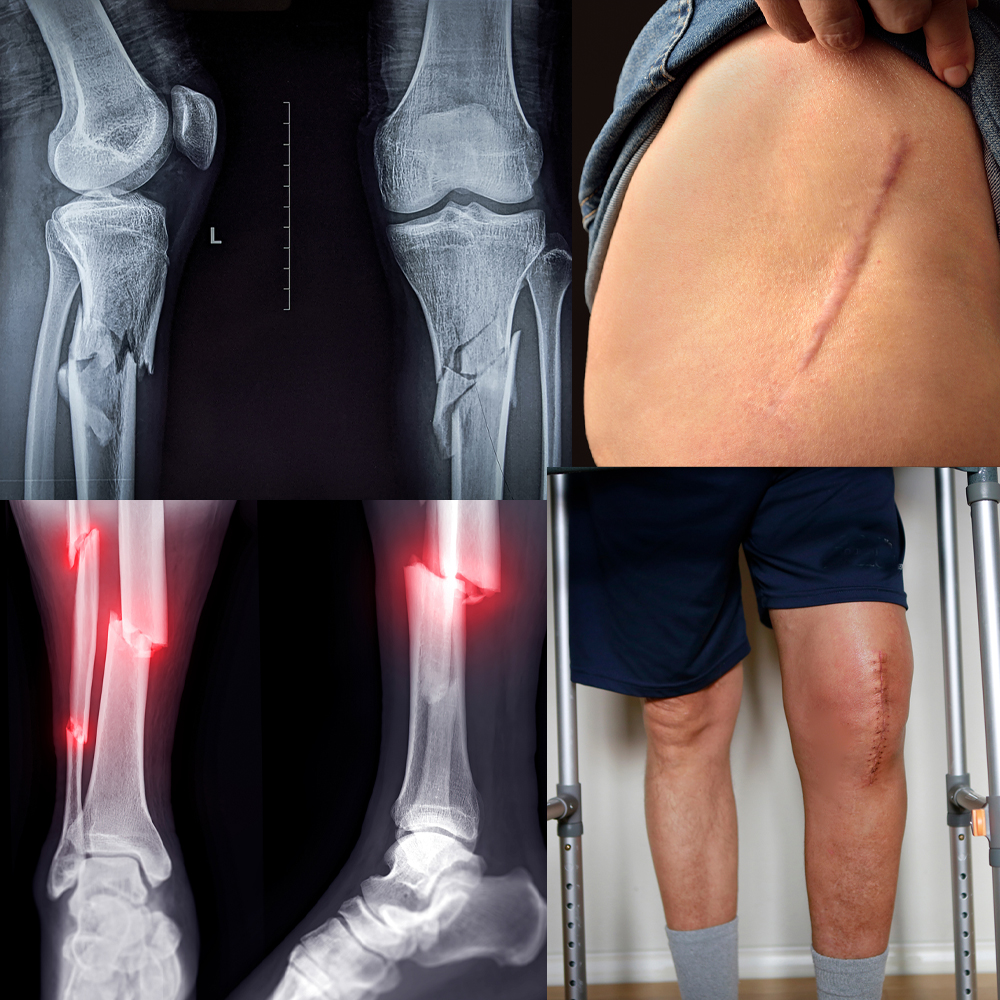

Surgery is only the beginning. Whether youโre recovering from joint replacement, spinal fusion, or a fracture, how you heal can shape your long-term outcome. PEMF and Infrared Therapy help speed recovery by reducing swelling, boosting circulation, and supporting deep tissue and bone repair at the cellular level. Healing Mats offers portable therapy mats for home use โ drug-free, clinic-free recovery support that fits your life. Perfect for post-op recovery, especially if you're older, have diabetes or osteoporosis, or are healing from a second surgery. Ready to heal stronger and faster? ๐ Learn more on our "What is PEMF" page ๐ Call (03) 6215 4777